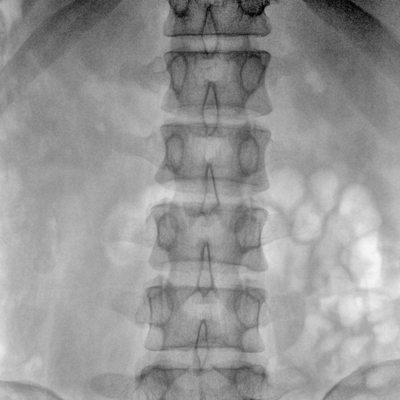

大尺寸动态平板探测器,高DQE、低噪声、图像清晰。采用多分辨率图像增强处理技术,不同部位不同图像处理算法,满足客户多样化的需求。